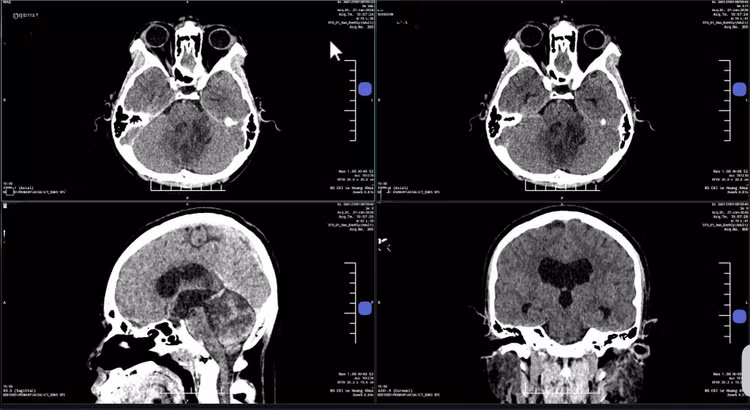

u-nao1.jpg

Bác sĩ dùng robot Modus V Synaptive tích hợp AI để loại bỏ khối u não cho bà Hạnh. Ảnh: Bệnh viện Đa khoa Tâm Anh

Hậu phẫu, bà Hạnh tỉnh táo, tiếp xúc tốt, hết đau đầu, lưỡi mềm và nói rõ hơn. Hình CT sọ não kiểm tra hậu phẫu cho thấy không chảy máu, không phù não, các cấu trúc vùng hố sau ổn định. Dây thần kinh số 12 bị chèn ép trước mổ vẫn nguyên vẹn, chưa có dấu hiệu tổn thương không hồi phục.